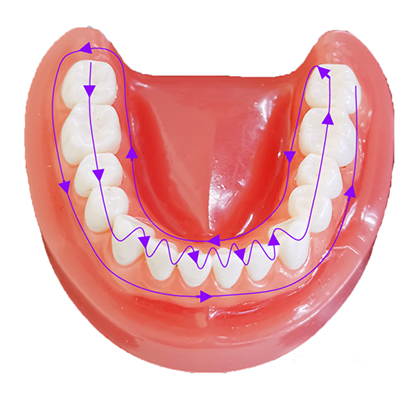

3. روش عملیات مسیر اسکن 1

این روش مسیر اسکن بر اساس یک مسیر S شکل چند بخش است. پس از تکمیل اسکن سطح فک، سطح باکال و سطح لینگوال ناحیه مولر در یک طرف قوس دندانی، سر اسکن به ناحیه قدامی و ناحیه مولر در سمت دیگر زخم میشود.

همانطور که در شکل بالا نشان داده شده است، روش S شکل را برای اسکن اتخاذ کنید، سمت فک قوس را به عنوان نقطه شروع، سمت فک - سمت زبانی - سمت لبی و باکال را در نظر بگیرید تا شکل S شکل بگیرد و اسکن را بچرخانید. در طول فرآیند اسکن به طور متوسط سر کنید تا مطمئن شوید که هر دندان اسکن شده است و به تدریج اسکن کل ردیف دندان را کامل کنید.

در نهایت، اسکن پرکننده کلید انجام میشود: آخرین دندان مولر، فاصله تماس بین هر دندان در قوس دندانی، موقعیت لثهها و موقعیت سریع نرمافزار.